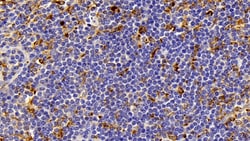

IBA1 Polyclonal Antibody for Western Blot, IHC (P)

Ionized calcium-binding adapter molecule 1 (IBA1), also known by its gene name AIF1, is a protein expressed predominantly by microglia in the brain and spinal cord. This protein belongs to the EF-hand calcium-binding protein family and plays a crucial role in microglial activation and migration in response to brain injury or neuroinflammation. IBA1's function is integral to microglial motility and phagocytic activity, facilitating the cellular response to pathogenic stimuli and promoting tissue homeostasis and repair in the central nervous system. IBA1 serves as a reliable marker for activated microglia in various neurological disorders, including Alzheimer's disease, Parkinson's disease, and multiple sclerosis, where increased expression correlates with disease progression and severity. The protein's structural features enable it to bind calcium ions, inducing conformational changes that activate signaling pathways essential for microglial function. Its expression is highly regulated by inflammatory cytokines, underpinning its role in neuroimmune responses. Due to its specific expression in microglia during pathological conditions, IBA1 is widely used in research as a marker to study microglial status and activity, and it remains a focal point for understanding microglial involvement in neurodegenerative diseases.Specifications

| Immunohistochemistry (Paraffin), Western Blot | |